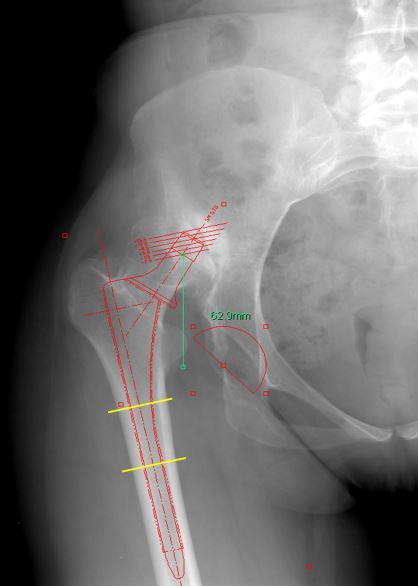

方法:在一项回顾性研究中,我们评估了24例非骨水泥全髋关节置换术的结果和并发症,共 24例(20例女性和4例男性)Crowe型IV型发育不良。采用非骨水泥全髋关节置换术结合转子下缩短截骨术,将髋臼假体放置在解剖学旋转中心的水平处。术后平均随访4.8年,对患者进行评估。

结果:平均的Harris髋关节评分从术前的 43 分提高到了最终随访时的 89 分(p <0.01)。 28 个髋中有12个(43%)发生了早期或晚期并发症或再次手术。28例转子下截骨术中有2例(7%)发生骨不连。有1例股骨柄松动,1个髋臼假体松动,1个髋臼内衬脱离。术后有4例髋关节脱位。在最后一次随访时,其余组件均固定良好。未发现坐骨神经损伤的病例。

结论:在髋关节发育不良继发高位髋关节脱位的患者中,非骨水泥全髋关节置换术结合股骨转子下缩短截骨术可以成功固定植入物和获得截骨部位愈合,平均术后Harris髋关节评分89分。 然而,这一类患者术后的并发症发生率显著高于骨关节炎的初次全髋关节置换术。